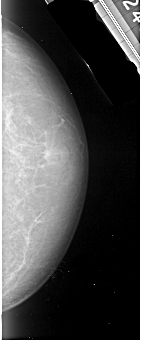

A_1003_1.RIGHT_MLO

RIGHT_MLO LINES 5371 PIXELS_PER_LINE 1951 BITS_PER_PIXEL 16 RESOLUTION 42 NON_OVERLAY

FILE: A_1003_1.LEFT_CC.OVERLAY

TOTAL_ABNORMALITIES 1

ABNORMALITY 1

LESION_TYPE CALCIFICATION TYPE PLEOMORPHIC DISTRIBUTION CLUSTERED

ASSESSMENT 4

SUBTLETY 3

PATHOLOGY MALIGNANT

TOTAL_OUTLINES 1

BOUNDARY